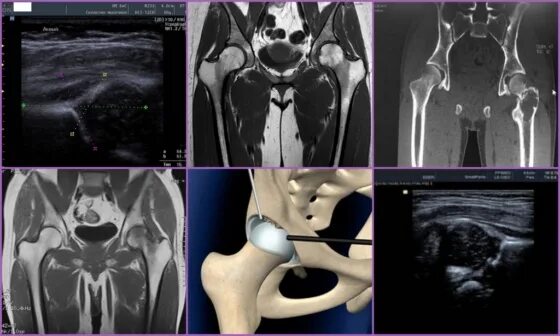

Рентген тазобедренный в двух проекциях